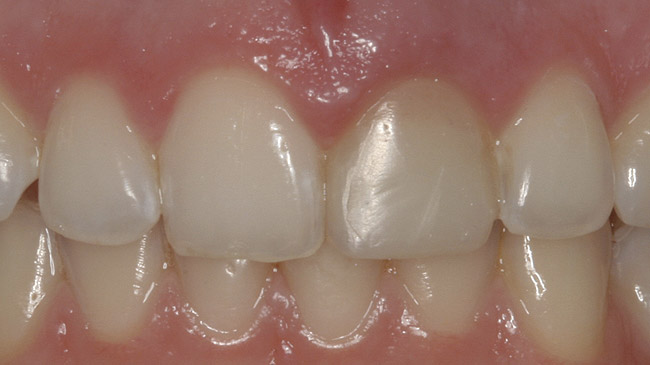

After the zirconia abutments were torqued to 20 Ncm, cotton and composite were used to cover the screw access openings. Figure 7 and Figure 8 show the finished feldspathic porcelain crowns on implants in sites Nos. 24 through 26, and on teeth Nos. 22, 23, 27, and 28; all crowns were cemented with dual-cure resin cement. Good remodeling of gingival architecture is also apparent in Figure 7. As predicted, the free gingival margin (FGM) on No. 23 is approximately 2 mm coronal to those of the adjacent implant crowns on Nos. 24 through 26 (Figure 7); as per the patient’s initial statement, this discrepancy was not an esthetic concern to her. Figure 9 shows the final post-restoration periapical view.

The final screw-retained crown was delivered and torqued onto the implant to 35 Ncm; the restorative dentist then sealed the screw access with a cotton pellet and composite (Figure 20 and Figure 21). Various views of the final crown are shown in Figure 22 through Figure 25, including a full-face photograph.

This patient faced a unique situation, perhaps not previously reported: retaining a healthy mandibular lateral incisor knowing this would create an esthetic compromise. Indeed, while the discrepancy in gingival-margin height is noticeable in retracted view (Figure 7), it does not show in full smile (Figure 8).

Figure 7  Finished feldspathic crowns, teeth Nos. 22, 23, 27, 28, and implant sites 24 through 26 showing good gingival emergence profile—post-cementation facial view.

Figure 7

Figure 8  Full smile—finished feldspathic crowns on teeth Nos. 22, 23, 27, and 28; implant crowns in sites 24 through 26; esthetic harmonization with opposing dentition.

Figure 8

Figure 22  Final zirconia crown, No. 9, in occlusion—facial view.

Figure 22